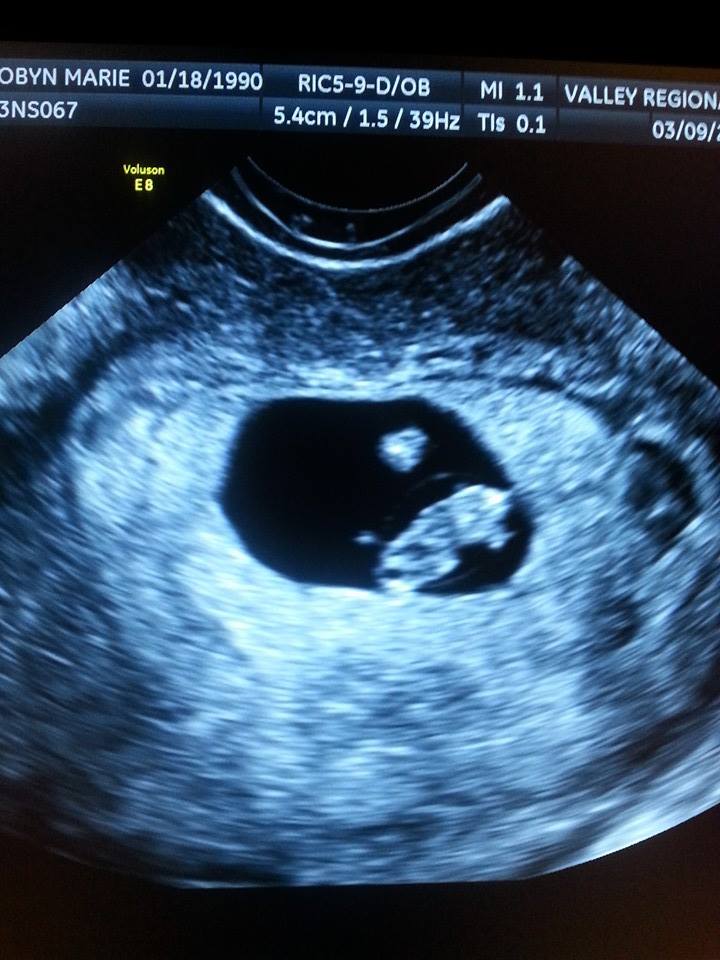

Baby Walton today (3/11) at 9w4d gestational age is +1 day! He even stretched his arm out during the U/S and we saw the heartbeat!! HR is 162 bpm so in love with this tiny thing!!